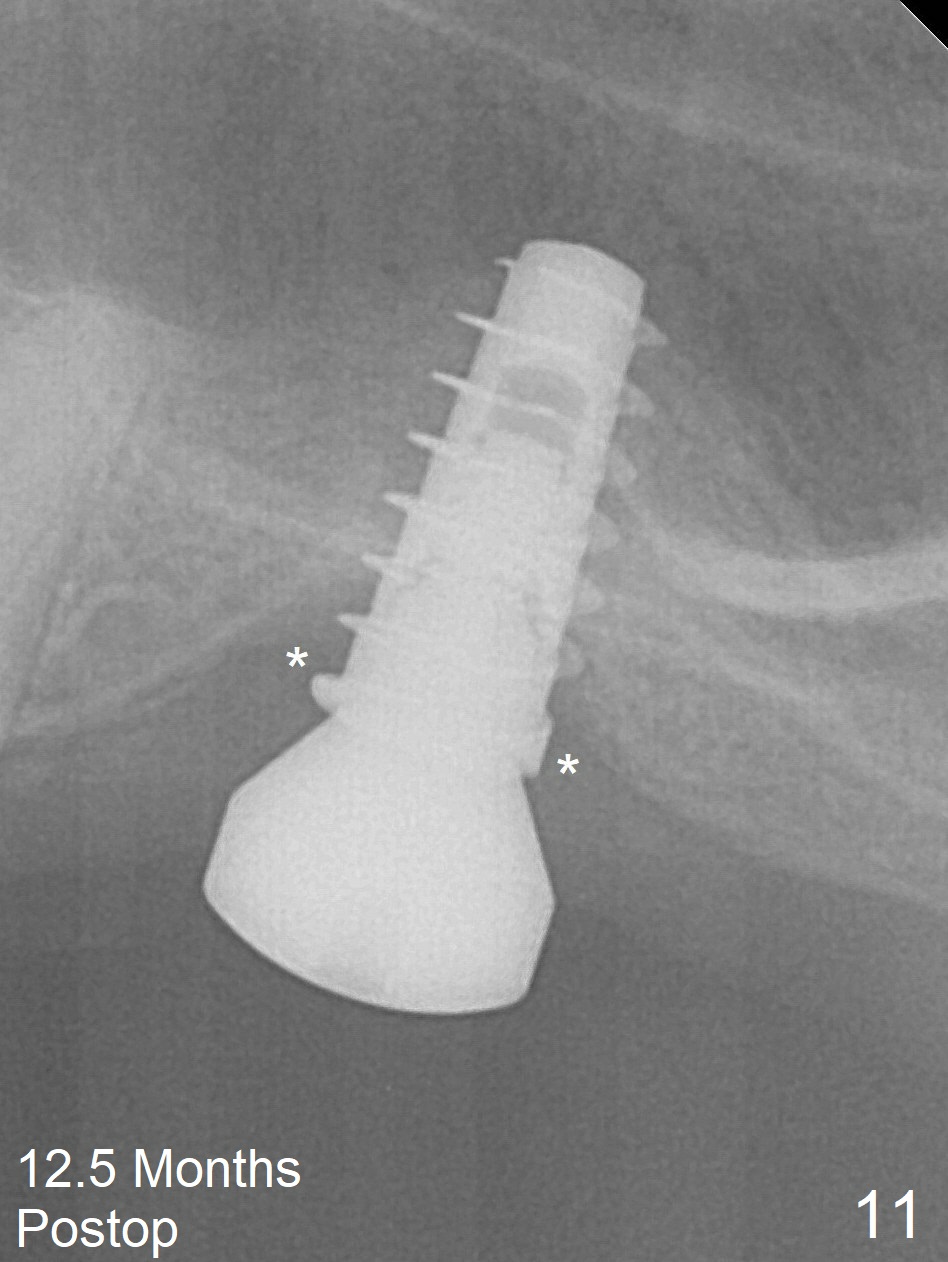

Three weeks later (approximately 8.5 months postop), the implant is found to be able to rotate when a 6.5x5.7(1) mm pair abutment is tightened with local anesthesia (there is pain associated with healing screw removal). After removal of the latter, the implant is placed deeper by hand retightening (Fig.10 arrow). Is it a better idea to use a new larger implant instead? The patient (53 years old) is scheduled to return for follow up in 3 months. In fact she returns 4 months later. The implant remains unstable and tender with loss of the crestal bone (Fig.11 *). It will be replaced with an implant (larger in diameter, but shorter) with SLA surface after debridement and bone graft. Change the trajectory so that the coronal end will be more mesial. Use a healing screw and try to close the wound. In fact the patient reveals history of osteoporosis.